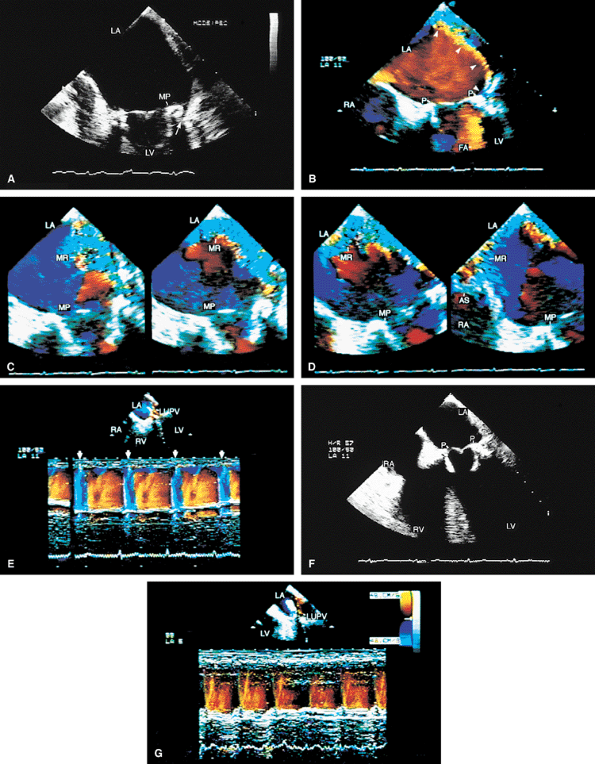

FIGURE 5.25. Porcine mitral prosthesis: cusp rupture. A. Marked bowing (arrow) of the prosthetic (P) leaflets into the left atrium caused by prolapse. There is no evidence of cusp rupture. B–F. Rupture of the cusps (arrowheads) is seen. Note prominent linear protrusion of the ruptured leaflets into the left atrium (LA). F. Coarse systolic flutter of a ruptured cusp (arrowhead). G. Torrential mitral regurgitation (MR), together with a large area of flow acceleration (FA), on the ventricular aspect of the prosthesis. B and C are from one patient; D–G are from another patient. H,I. Another patient with porcine cusp prolapse and rupture (arrowhead in H), with severe MR (arrowheads) and prominent FA in I. J–L. Rupture of thickened porcine mitral cusps (arrowheads in J,K) with severe, eccentric MR (arrowheads in L) through the prosthesis (P). M. Another patient with porcine (P) cusp rupture with severe MR (arrows) shown in both color two-dimensional and M-mode images (arrows). N. The arrow points to severe valvular MR from cusp rupture; arrowheads show associated severe paravalvular MR. O,P. Gross specimens show porcine prosthetic cusp rupture. LA, left atrium; RA, right atrium; LV, left ventricle; RV, right ventricle; LVOT, left ventricular outflow tract; RVO, right ventricular outflow tract. |